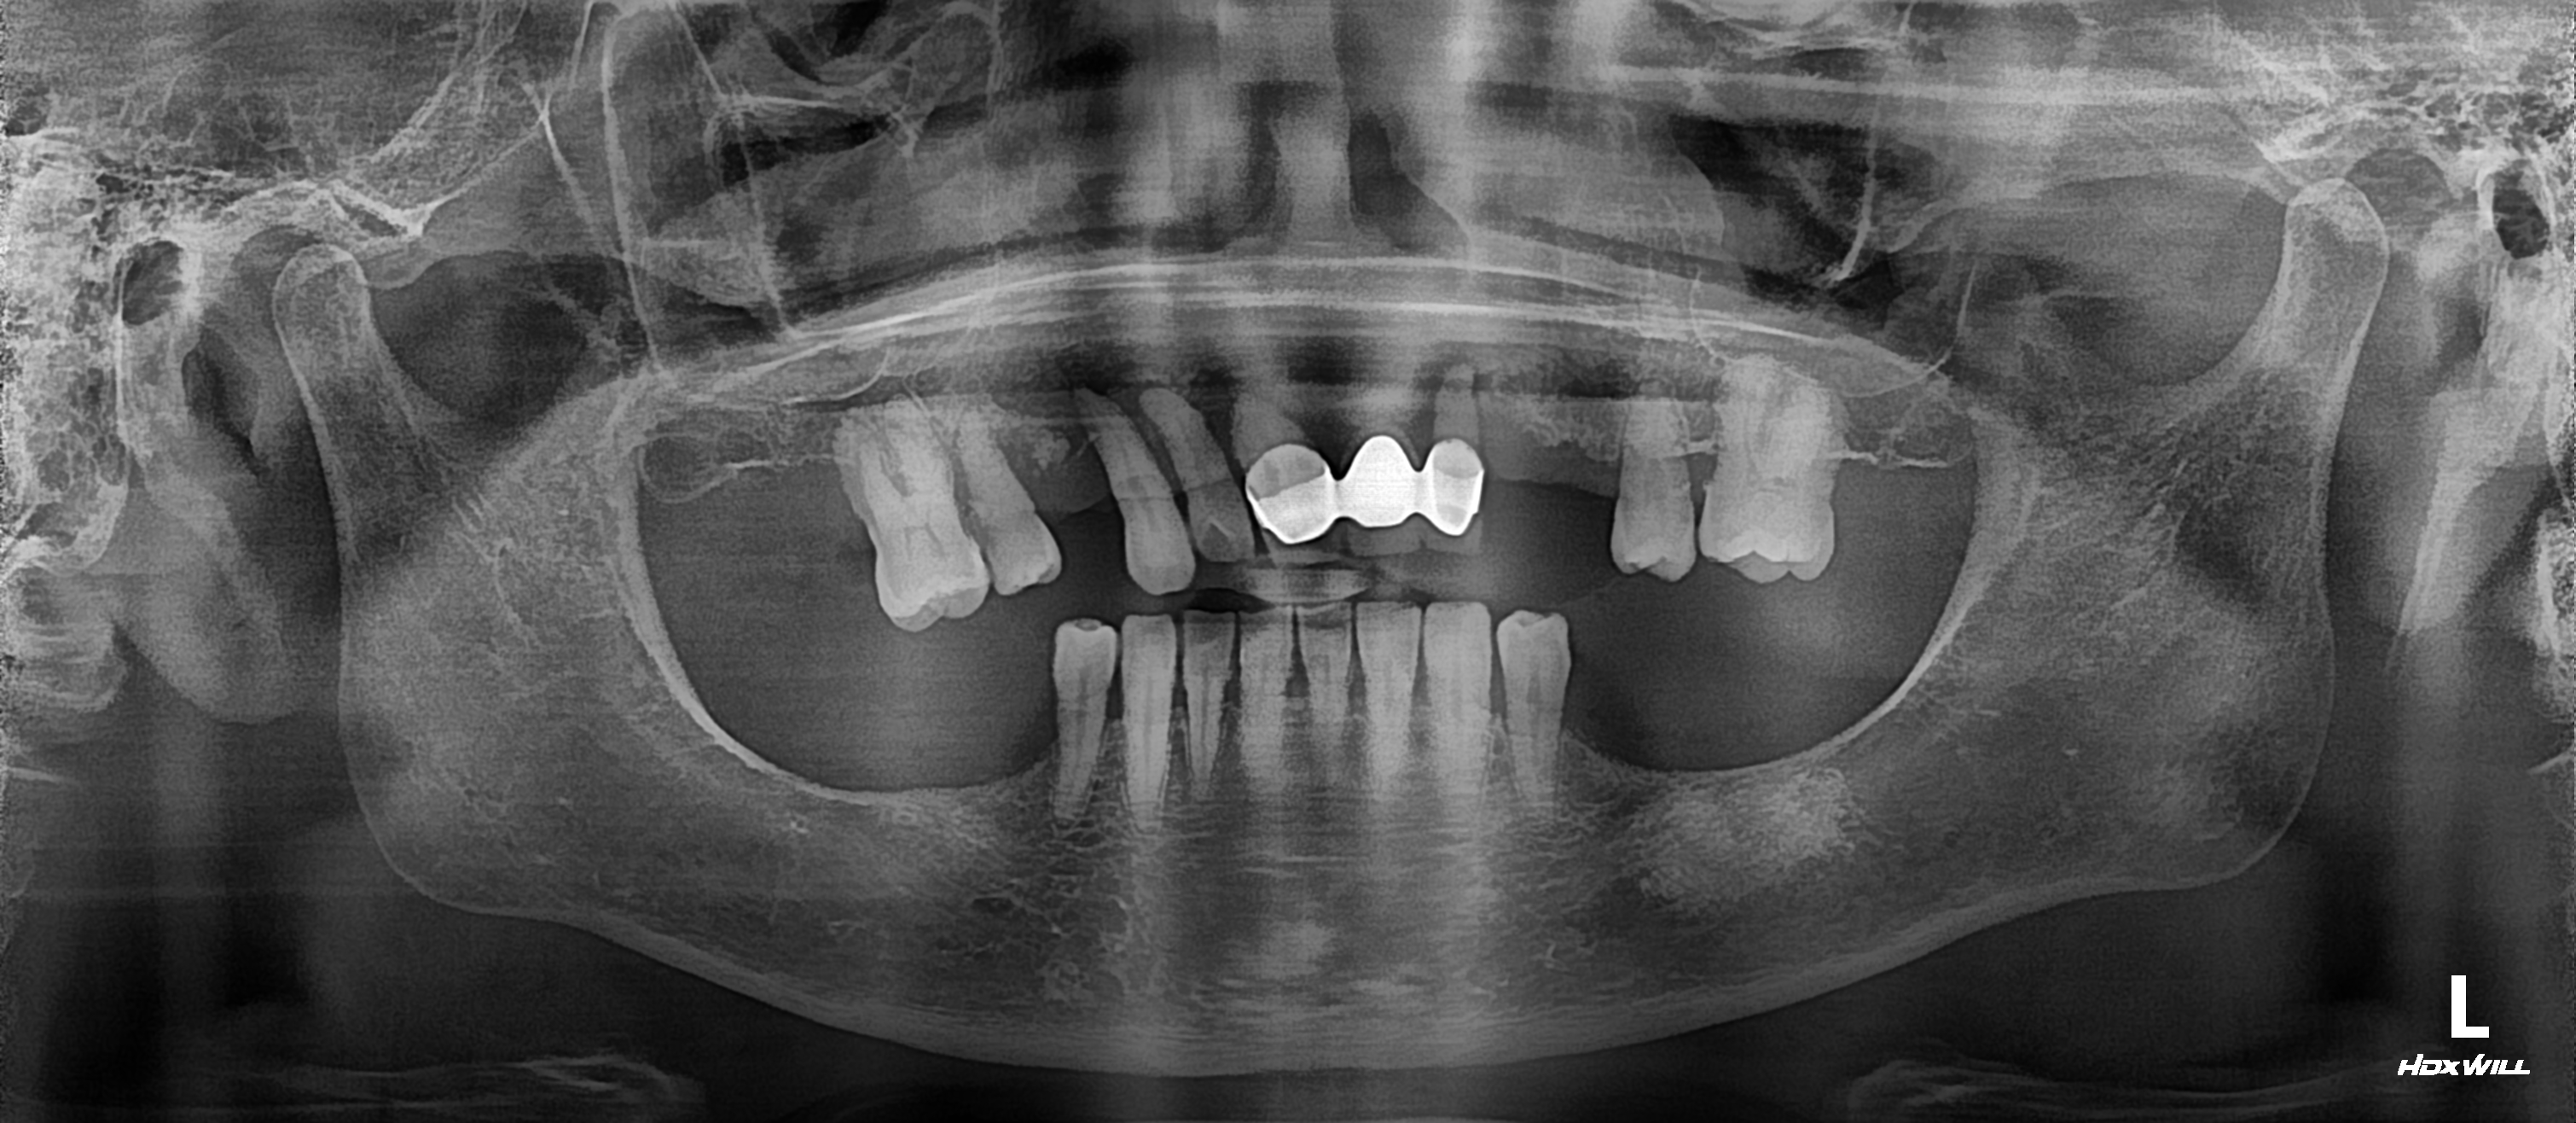

"오래전부터 어금니가 하나씩 빠지고 부러져서 식사를 잘 할수가 없어요"

엑스레이를 보시면 양측 위아래 어금니 부위가 모두 빠져서 앞니부위로 식사를 하신 환자분입니다.

앞니부위로 식사를 하면 앞니끼리 많이 충돌하여 잇몸뼈가 내려가거나 앞니가 마모되는 일이 발생합니다.

이런경우 과거의 경우는 부분틀니를 사용하였지만 최근에는 임플란트를 식립하여 구치부 교합을 형성하고 교합을 안정화시켜주면

저작도 편하고 앞니의 마모를 예방할수 있습니다.